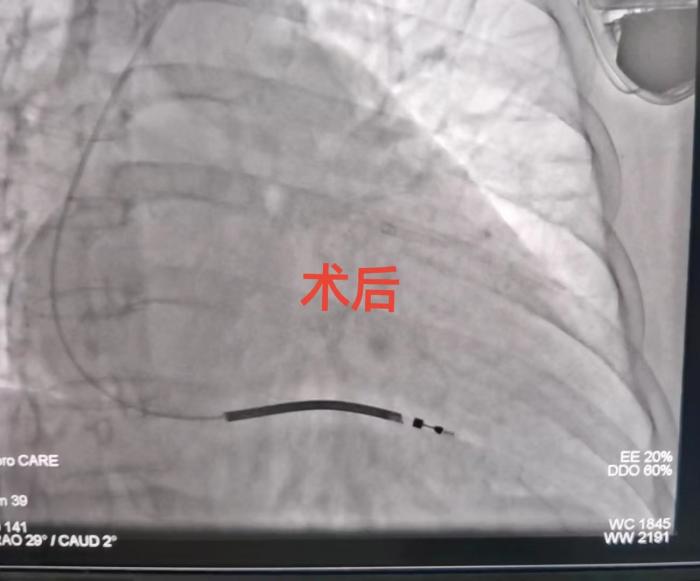

与患者及家属详细沟通并征得患者同意后,心内二科手术团队周玉庆副主任医师、李华锋主治医师在局麻下为李阿姨行经腋静脉径路ICD植入术,手术历经1小时圆满完成。术后患者恢复良好,术后1天便可自行下床活动,患者家属表示手术后患者的精神较前明显好转,装了除颤器家里人都不用提心吊胆了。